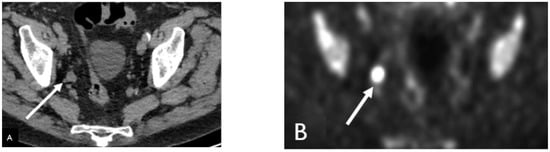

Detection of Loco-Regional Disease and Distant Metastases